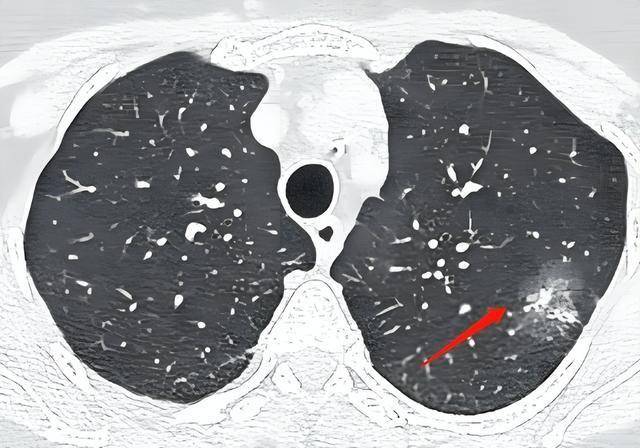

实际上,肺结节本质上是肺组织内直径不超过3厘米的局灶性密度增高影像,绝大多数体积<1厘米,无任何症状。

现代影像学进步让“结节”变得无所遁形,但恶性风险却远低于想象。研究显示,首次筛查肺结节中,仅约2-5%最终诊断为肺癌,其余全部为各种良性改变(如炎症性结节、钙化、纤维增生等)。国外“大规模筛查随访10年数据”表明,大部分小结节随时间并不增长,有的甚至会自发消失。